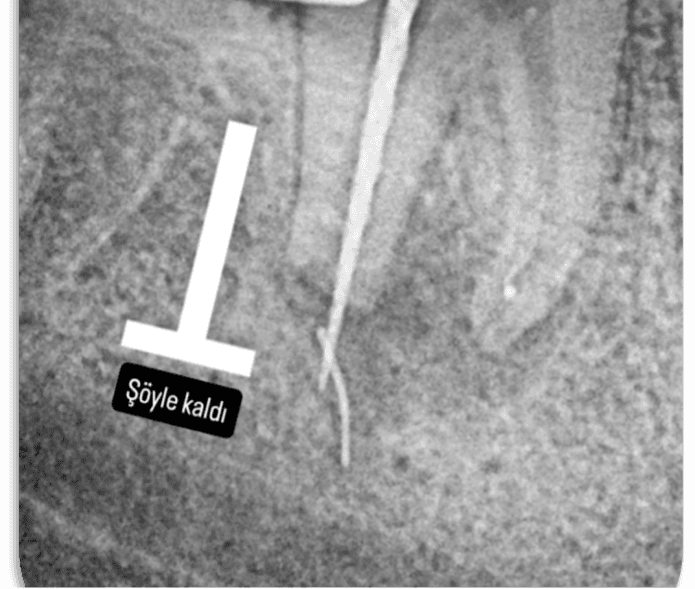

Alınan radyografta eğenin konumu teyit edildi ve bölgedeki granülasyon dokusu ophtalmic forseps ile eğe görünecek şekilde temizlendi. Kanalın apikali paper pointle kurutulduğunda eğenin koronal kısmı görüldü ve tel ilmik tekniği ile çıkarma işlemine geçildi. Tel ilmik ile eğe kökün dışında yakalandı ancak yakalama sonucu eğe kökün uzun aksı boyunca 90 derece açı yapacak şekilde takıldı (RESİM 7) ve koronale çekilemedi.

RESİM 7: Tel ilmikle yakalanan eğe görseldeki gibi köke dik konumda kaldı